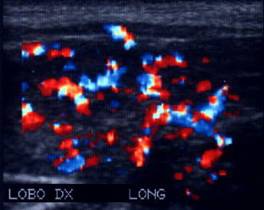

Femeie de 36 ani. Cunoscuta cu maladie Graves. La un

an dupa prima tiroidectomie totala pentru neoplazie papilara multifocala cu

metastaze in ganglioni (pT4b N1 M0).

Mica formatiune nodulara medial de carotida dreapta (0,2 cc), marcat

hipoecogena.

Tireoglobulina: < 2 ng.

Examen citologic: carcinom papilar.

Aceeasi pacienta - hipervascularizatie interna la doppler color si powerdoppler